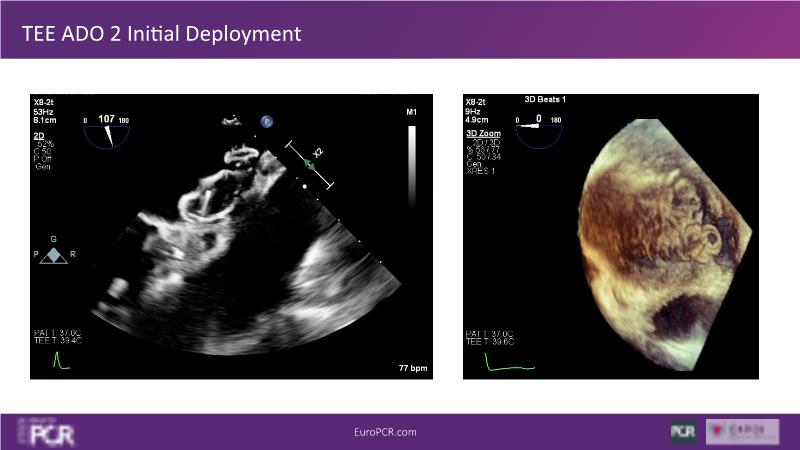

Explore this session to discover the latest innovations in interventional cardiology images, including the benefits of artificial intelligence and angio-CT in PCI/SHD procedures. Learn about Alphenix Evolve and the initial experiences with AI imaging in daily cathlab practice, alongside intraprocedural angio-CT guided LAAO, and engage in discussions on meaningful tools that can transform patient care.